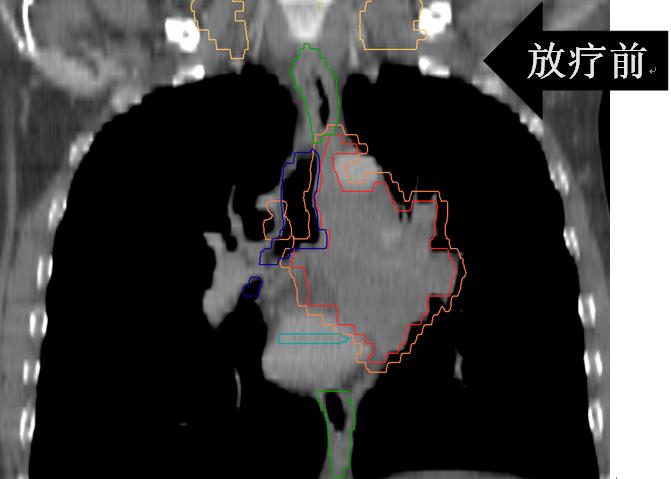

• (肺及纵隔病灶)iGTV1/GTV1/CTV1/70Gy/60Gy/50Gy/20F;

• (锁骨上病灶)GTV2/CTV2/60Gy/50Gy/20F。

放疗后患者咳嗽、咳痰、左肩背部疼痛、痰中带血、胸闷、气短完全缓解;继续于外院行综合治疗并定期随访观察。

有图有真相:放疗效果显著!是不是疗效好就应该损伤重呢?肺损伤?